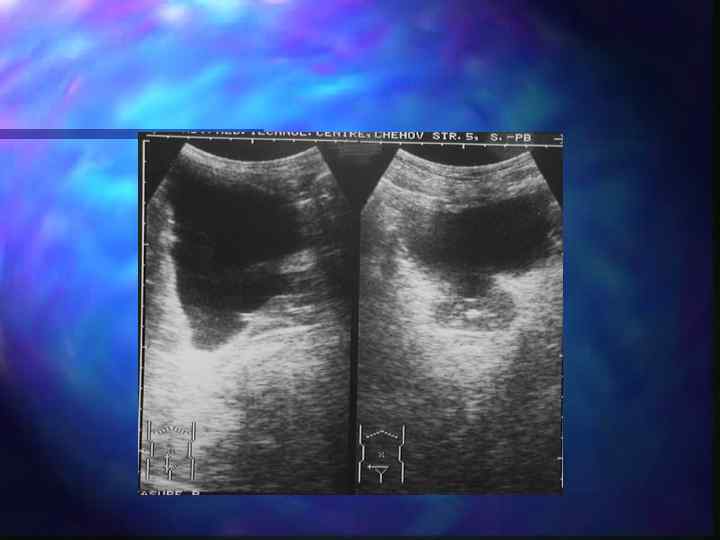

Абсцесс предстательной железы n Самое частое осложнение острого простатита n Эхографическая картина зависит от стадии созревания

Абсцесс предстательной железы Фомирование абсцесса- стадия инфильтрации n Асимметрия долей n Гипоэхогенный участок без четких границ n Очаговое снижение васкуляризации

Абсцесс предстательной железы Гнойно-деструктивная стадия n Неоднородное содержимое, постоянно меняющееся при динамическом контроле n Эффект дорзального усиления n Гиперэхогенная капсула n Прогрессирующее обеднение кровотока n УЗАГ усиленный периферический кровоток по типу «пылающего кольца»

Абсцесс простаты

Абсцесс предстательной железы ЭДК В-режим